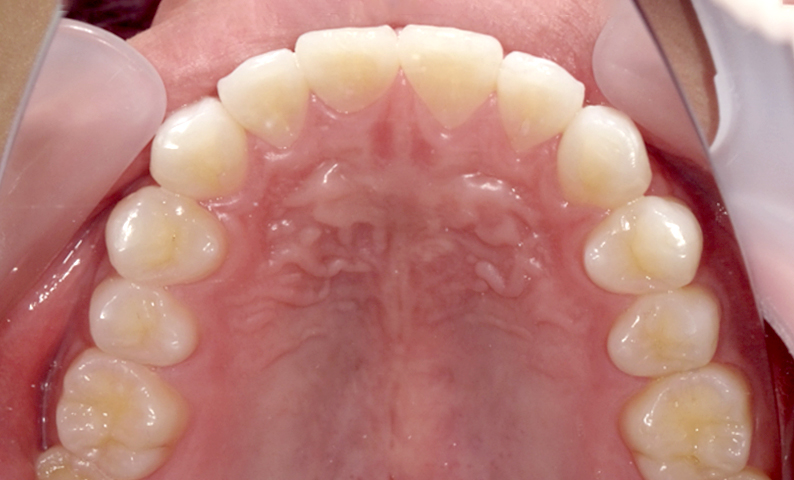

| 治療前 | 治療後 |

|---|---|

|